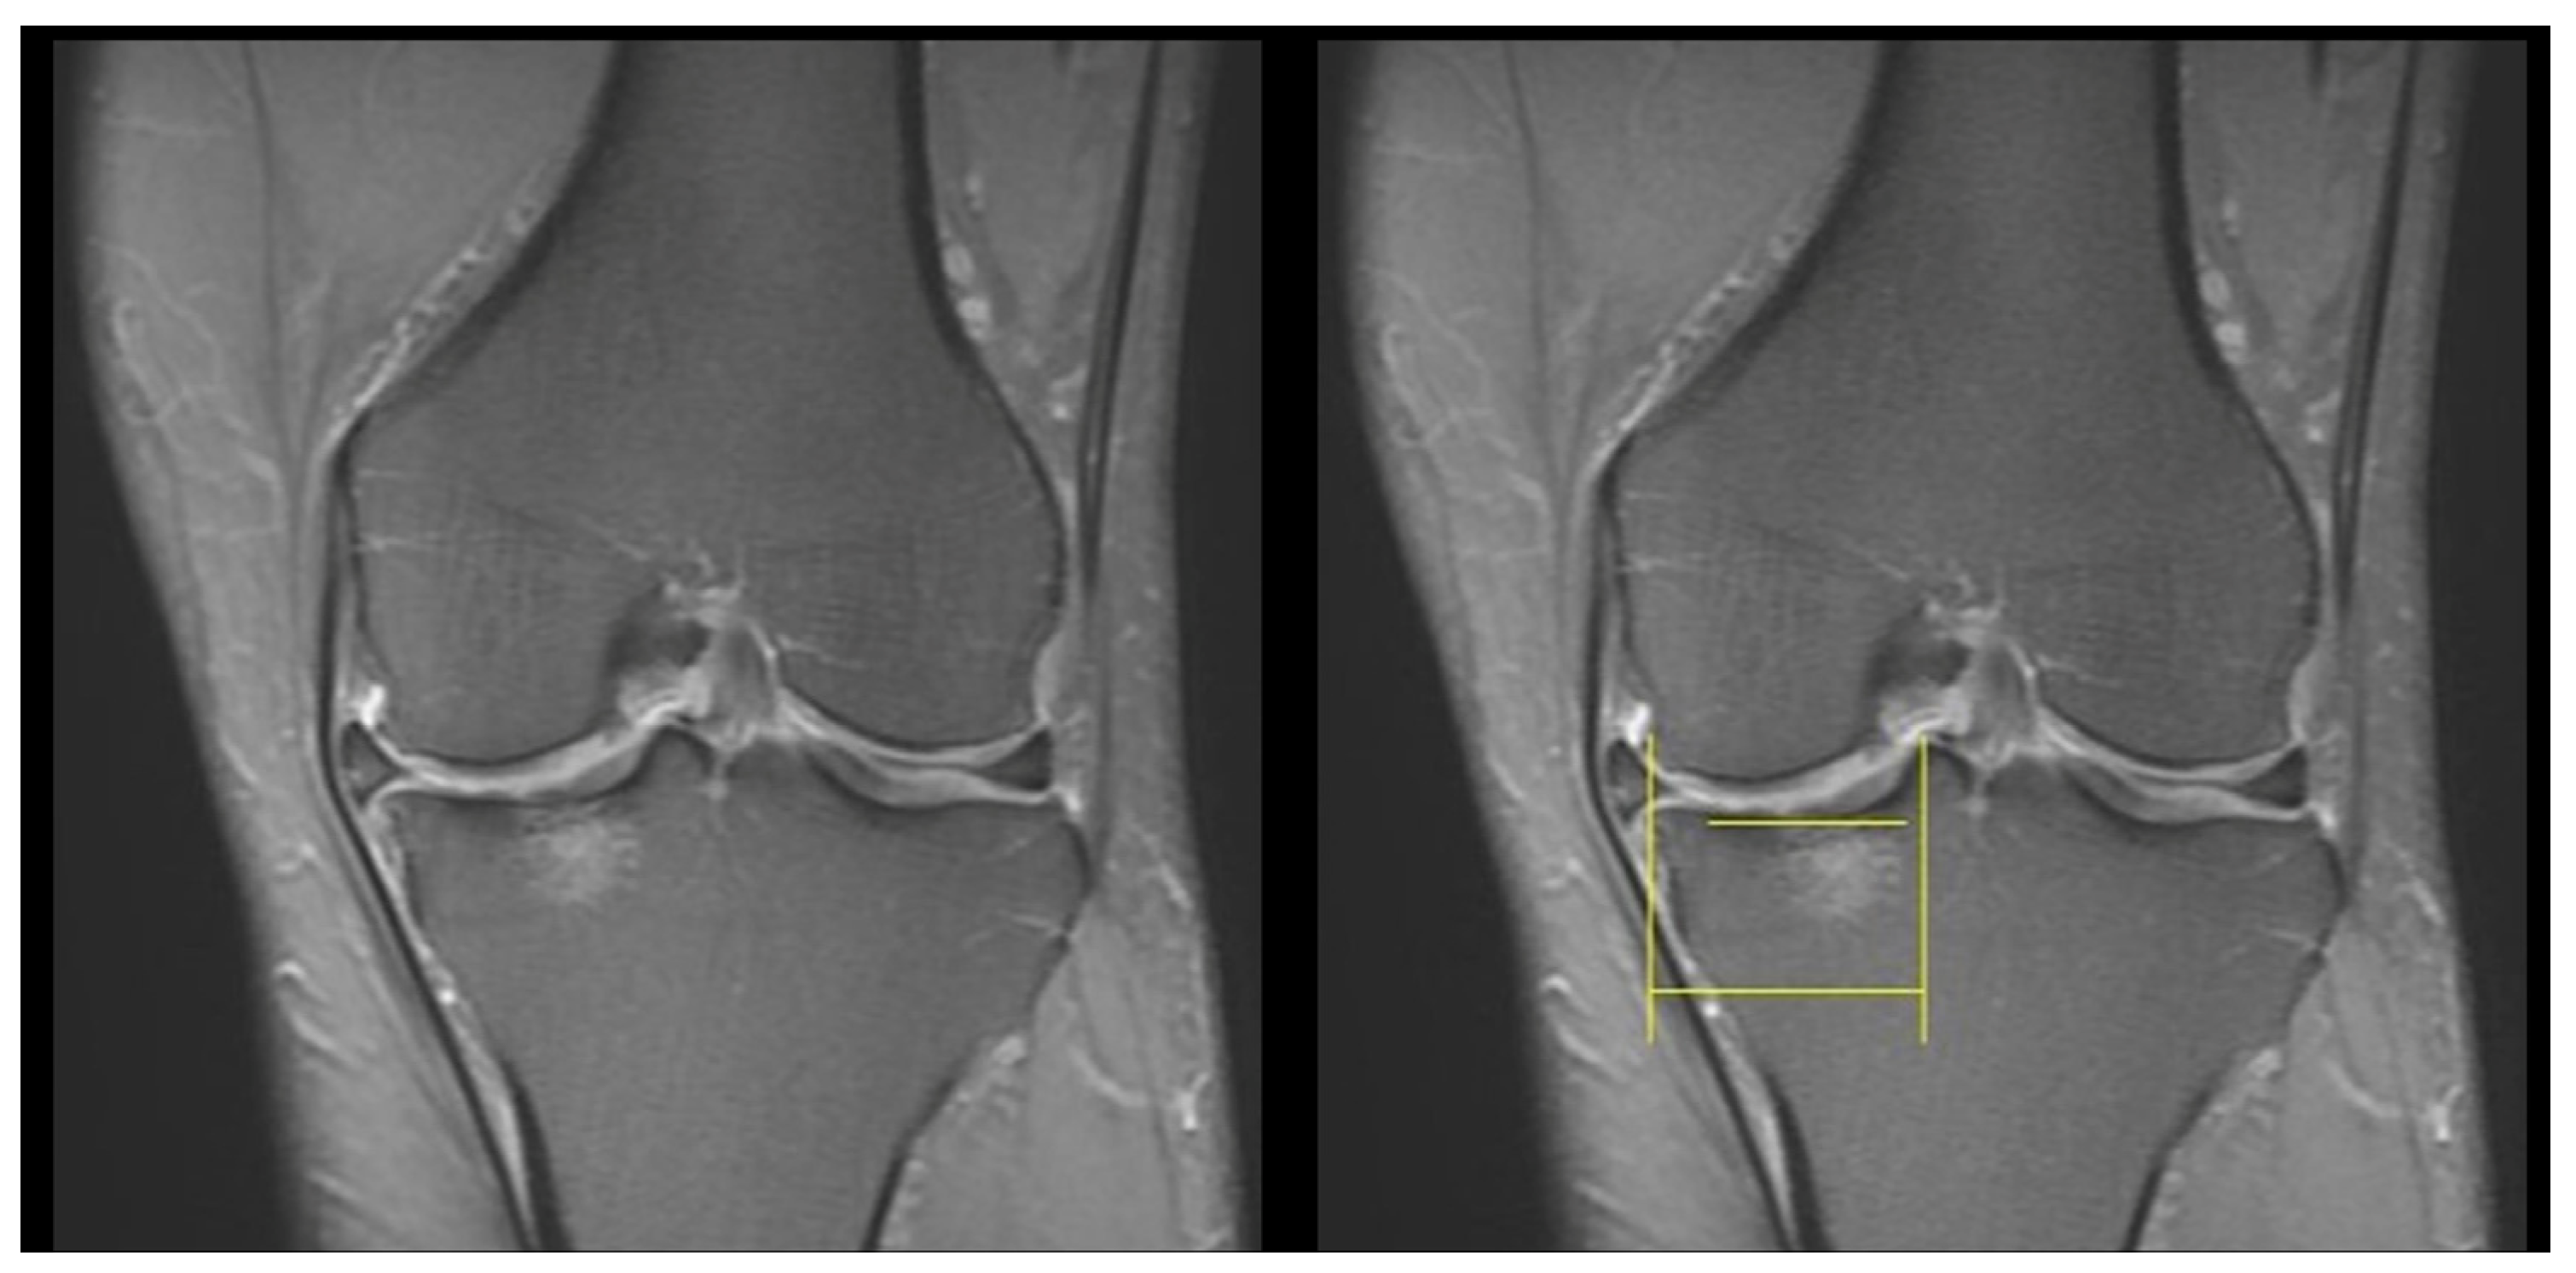

2.2.4. Knee OA Progression Grading